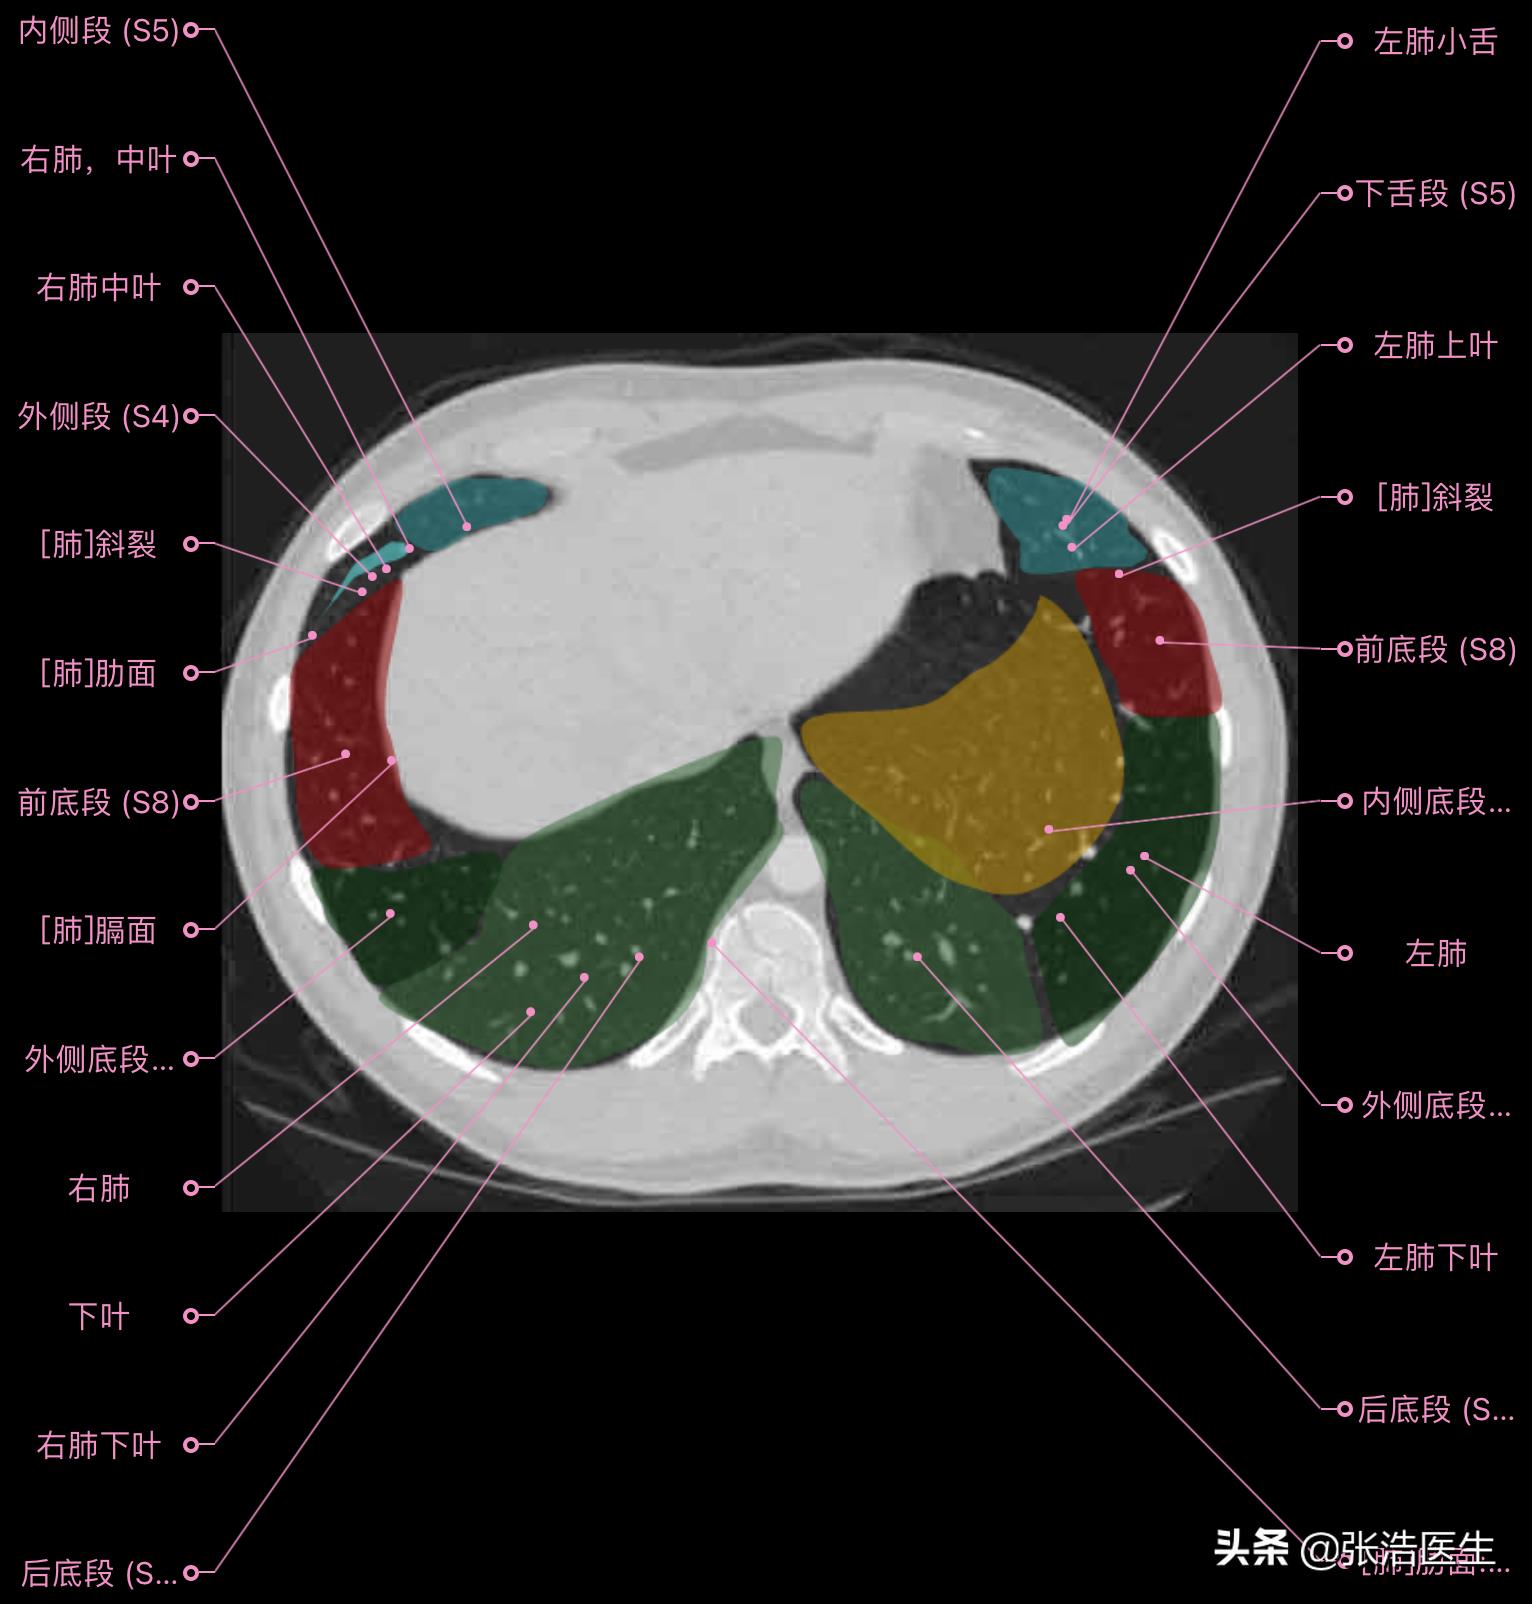

肺部CT横断面高清解剖图谱(图层5)